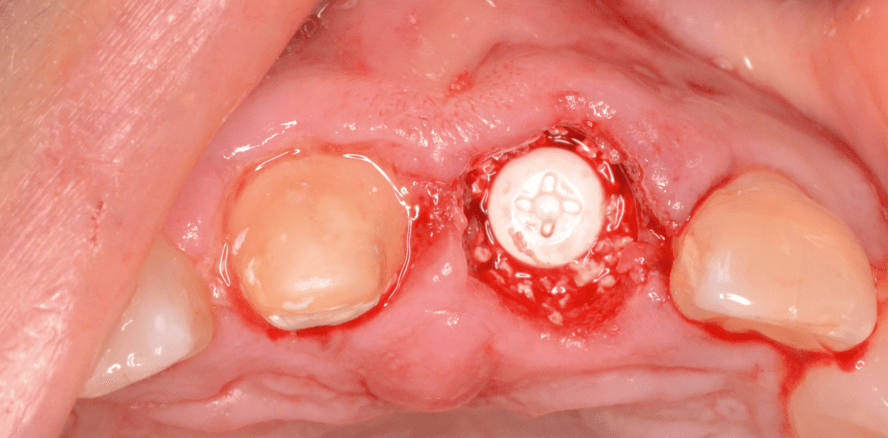

Foto: Dr. Volker Opitz

Das Fallbeispiel 2 zeigt den klassischen Verlauf einer Sofortimplantation in Regio 21. Der betreffende Zahn 21 musste aufgrund persistierender Beschwerden nach Wurzelbehandlung und WSR sowie zunehmender Lockerung entfernt werden (Abb. 2a–c). Das Implantat wurde nach komplikationsloser Extraktion leicht angewinkelt in der palatinalen Wand verankert, im vestibulären Bereich wurde vor und nach der Implantation marginal augmentiert (Abb. 2d–g). Nach circa fünf Monaten Einheilung erfolgten die Freilegung mittels Rolllappentechnik (Abb. 2h) und die anschließende Versorgung mit Zirkoniumdioxid-Abutment und individuell verblendeter Zirkonkrone auf Zahn 11 (Abb. 2i–k).